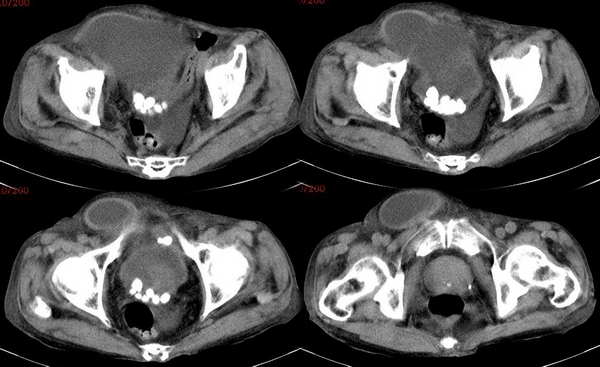

男性,90岁,腹部包块20余年.

右下腹囊性病变,其下部可见一堆牙齿样钙化影,囊下极疝入右腹股沟,病史20年,首先考虑良性畸胎瘤。

盆腔巨大囊性占位,其后下方多个小圆点状钙化,病灶向前下方突出于耻骨联合前方。充盈欠佳的膀胱受压后移。考虑畸胎瘤并腹壁疝,老年性骨质疏松。

下腹部巨大囊性占位,囊下极疝入右腹股沟。充盈欠佳的膀胱受压后移,膀胱内见多发结石。

1.下腹部囊肿,来源待定,淋巴管?肠系膜?

2.膀胱多发结石,结合b超,同意“最好作俯卧位扫描,看高密度灶的位置有没有变化.”